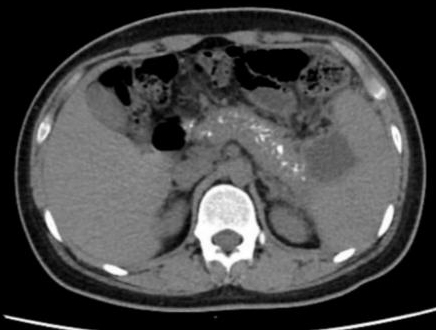

1 资料与方法患者男,17岁,主因“反复腹痛2年,加重伴发热2 d”来诊。患者于2019年起常于进食后出现腹部不适、纳差、腹痛,服用“胃药”对症处理后可好转,此后反复发作,频繁时半月发作一次。2020年9月下旬患者进食油腻食物后出现脐周及左中腹部胀痛,无恶心、呕吐,当地医院腹部CT提示:慢性胰腺炎急性发作,经对症治疗后2~3 d好转,此后每月有类似症状发作一次。2021年1月18日到本院基本外科门诊查胰腺功能,血清淀粉酶73 U/L,脂质624 U/L; 血钙正常; 血脂4项正常; 检查肿瘤指标,CA-125: 46.9 U/mL(升高),余为阴性; 甲状旁腺素正常; 血清IgG四项:IgG3 154 mg/L(降低),IgG4 1 600 mg/L(升高)。腹盆CT示胰腺多发钙化,胰尾囊肿形成(图 1)。1月22日患者进食汤面后出现腹部不适、纳差、乏力。1月24日晨起后出现腹部剧烈疼痛,伴发热,最高37.6℃,无恶心呕吐,无腹泻,于本院急诊就诊查血象正常,超敏C反应蛋白142.15 mg/L,胰腺功能:血清淀粉酶130 U/L, 脂质1 127 U/L。行腹盆CT检查示:胰腺饱满伴多发钙化,胰周脂肪密度稍增高,可见多发索条影,符合慢性胰腺炎改变(图 2)。予厄他培南抗感染及抑酸、补液等支持治疗后症状略好转,于1月26日收入本院急诊留观继续治疗。既往史:早产儿(32周),右桡骨小头骨纤维瘤术后,过敏性哮喘。个人史:否认饮酒史。家族史:父母体健,无其他特殊情况。

| 图 1 患者2021-01-19腹部CT |